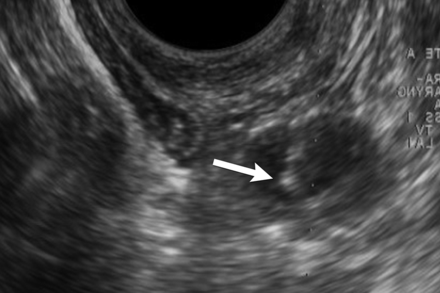

A large 4.3 × 2.5 × 1.9 cm left lateral retropharyngeal mass was found on restaging CT and PET/CT in a 38-year-old woman with a history of PTC. TOUS-FNA was performed, and cytology revealed benign reactive hyperplasia. There was clinical concern for lymphoma; therefore, a core biopsy was performed. The diagnosis of lymphoma was excluded, and the diagnosis was confirmed as a benign reactive lymph node (Fig 4).

True-negative cytology. A 38-year-old woman with a history of papillary thyroid cancer and left retropharyngeal mass. A, Axial contrast-enhanced CT scan shows an enlarged left retropharyngeal node (arrow). B, Axial PET/CT shows that the enlarged left retropharyngeal node has mild FDG avidity (arrow). Transverse (C) and sagittal oblique (D) sonography reveals an enlarged hypoechoic left lateral retropharyngeal node measuring 2.5 × 4.3 × 1.9 cm. E, Transverse color Doppler sonography shows the vascular flow of the lesion (white arrow) and its relationship to the internal carotid artery (black arrowhead) and internal jugular vein (black curved arrow). F, Transverse sonography during biopsy of the mass documents placement of needle tip (arrow) within the lesion before and during aspiration. Cytology revealed benign reactive hyperplasia.